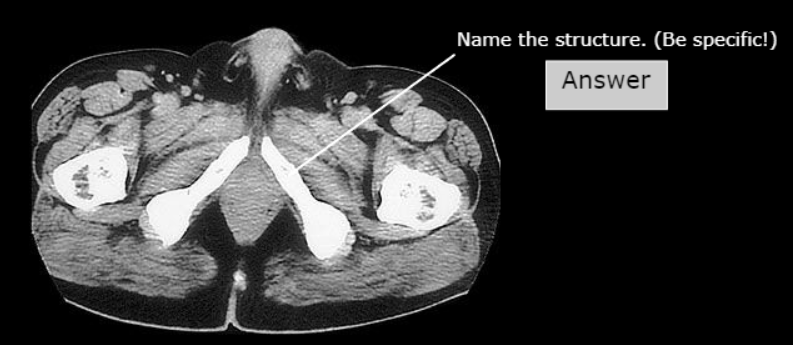

Corpus Cavernosum

Corpus spongiosum